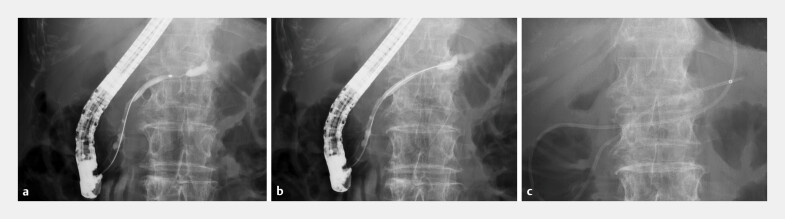

Abstract Image